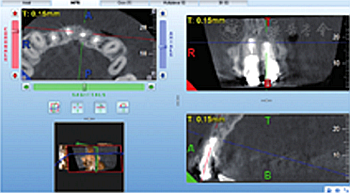

見圖8,圖9,圖10,圖11。分別于術(shù)后3、6個月時復(fù)查根尖X線片,8個月時復(fù)查錐形束CT并分別進行臨床檢查。復(fù)查結(jié)果顯示根尖病變已愈合,根尖無明顯低密度影。臨床檢查叩診正常,無松動,牙齦位置無明顯變化。

圖11 術(shù)后8個月復(fù)查錐形束CT截面顯示患者根尖病變已愈合